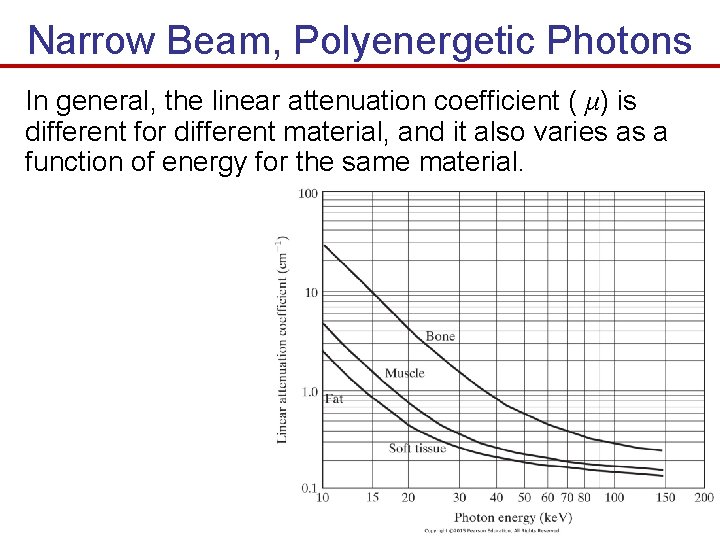

Narrow Beam, Polyenergetic Photons In general, the linear attenuation coefficient ( μ) is different for different material, and it also varies as a function of energy for the same material.